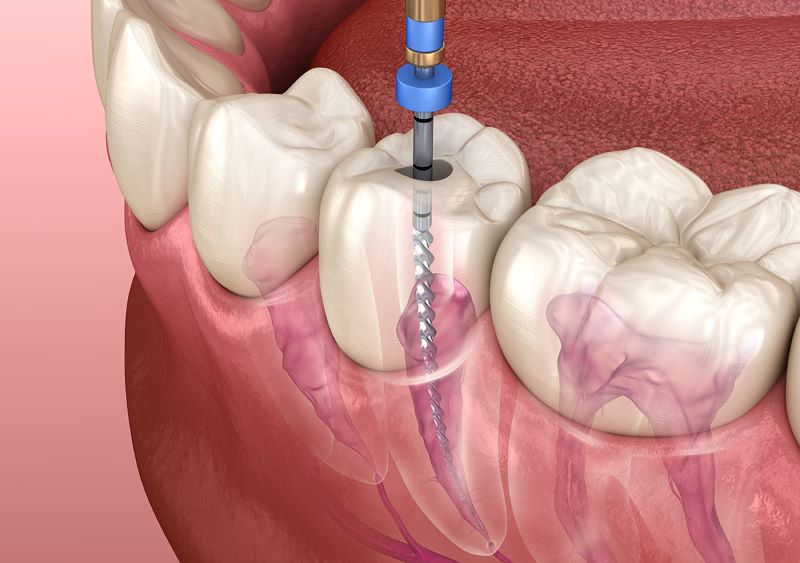

درمان ریشه دندان، که معمولاً با عنوان عصب کشی دندان در ونک شناخته میشود، یکی از روشهای حیاتی برای حفظ...